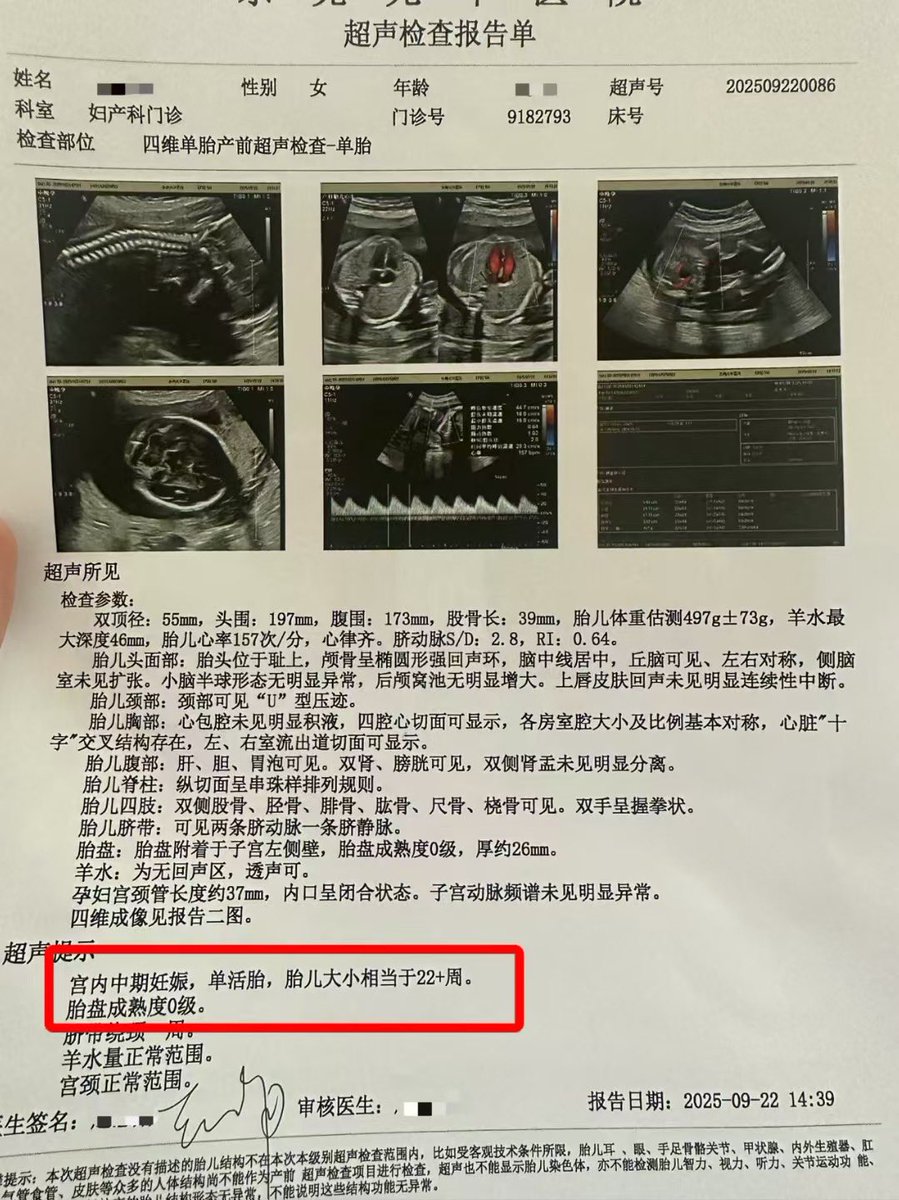

![代孕.HIV.洗精.国内代孕机构 (@wangjb168) on Twitter photo 【报喜篇】

🎉双份礼物,已签收!

老大6.2斤(实力派),老二4.9斤(小巧担当),从此进入“永动机”育儿模式🔋 双倍可爱😆 恭喜[庆祝]

#双胞胎 #试管婴儿 咨询微信:a18025307951

#广州代孕 【报喜篇】

🎉双份礼物,已签收!

老大6.2斤(实力派),老二4.9斤(小巧担当),从此进入“永动机”育儿模式🔋 双倍可爱😆 恭喜[庆祝]

#双胞胎 #试管婴儿 咨询微信:a18025307951